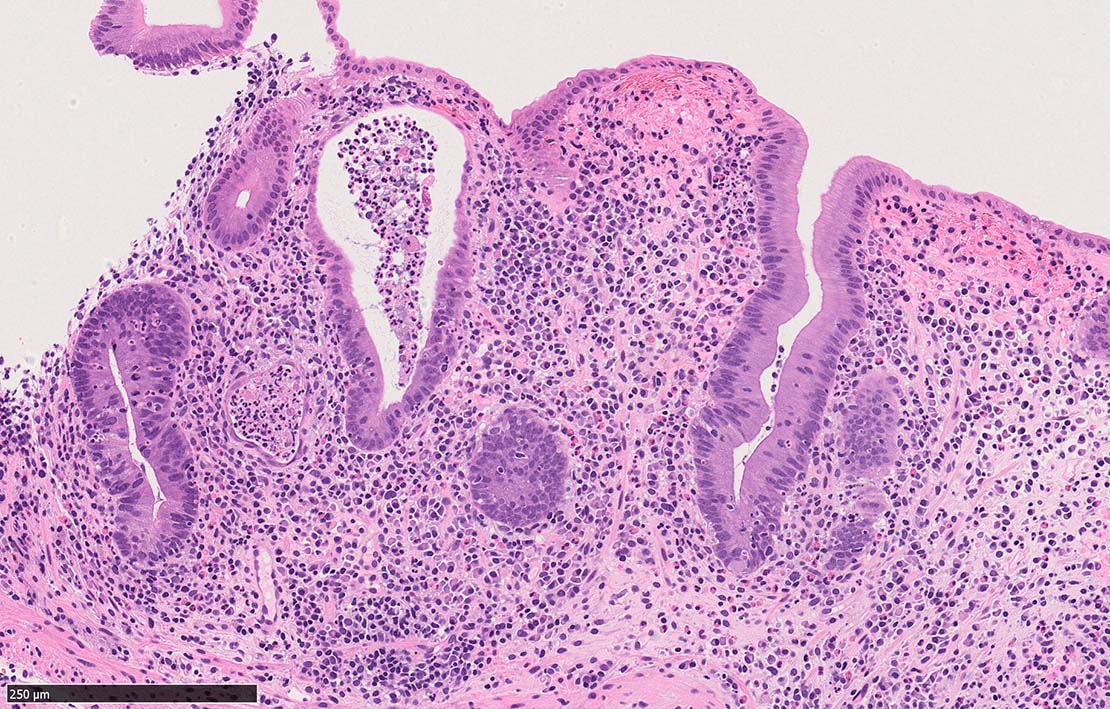

Case presentation

びらんを示す結腸粘膜. 陰窩はdeletion, 萎縮, distortionを呈する. 粘膜固有層には密な慢性炎症がみられ, 好酸球浸潤も多い.粘膜筋板へも炎症細胞浸潤が及ぶ.

UCのような, crypt abscess, cryptitisが認められる. 特徴的な所見として, apoptosis bodiesの増加が見られる.

陰窩に多数のapoptosis bodiesを認める.